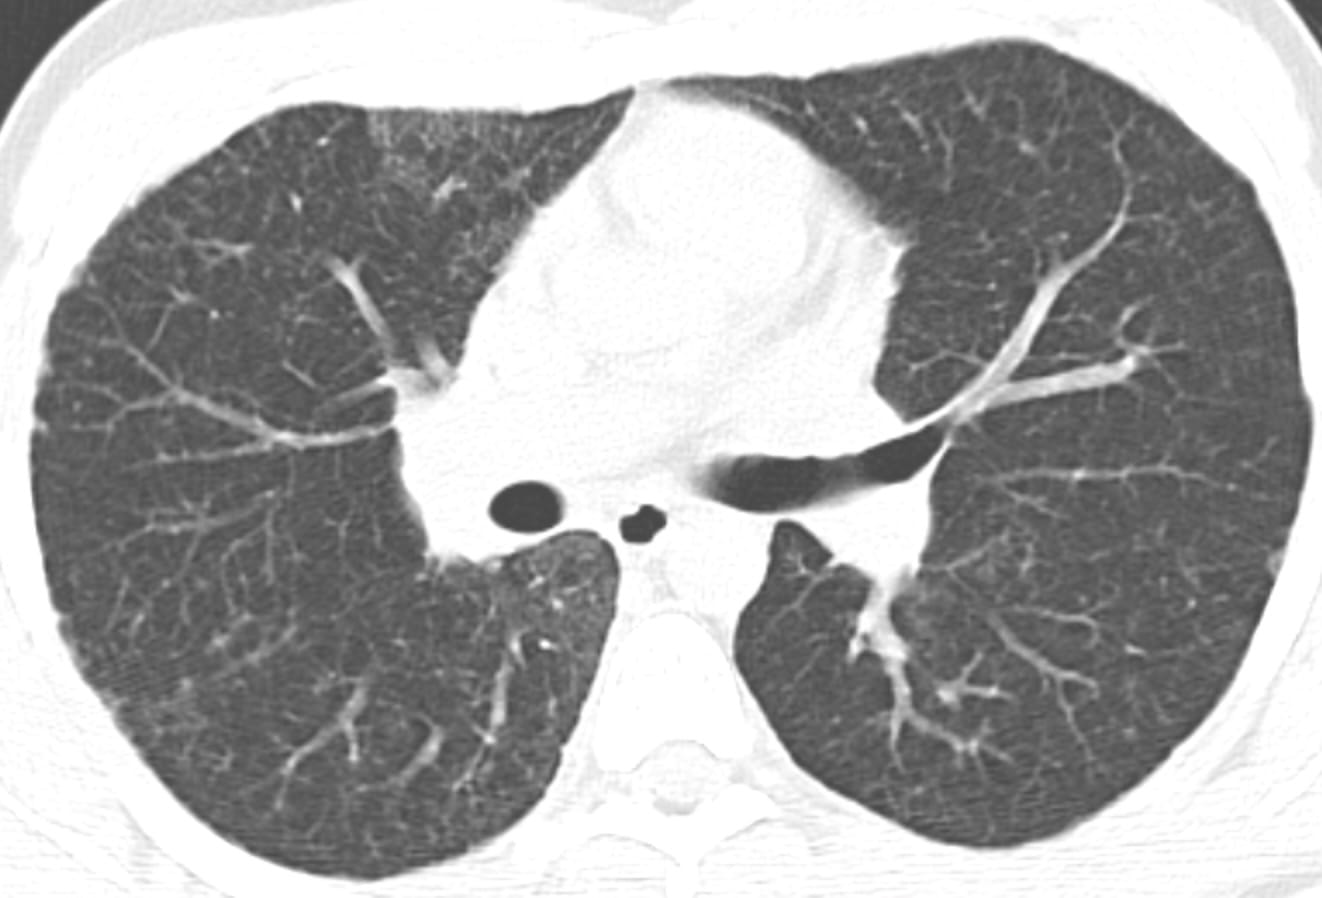

- Usual Interstitial Pneumonia